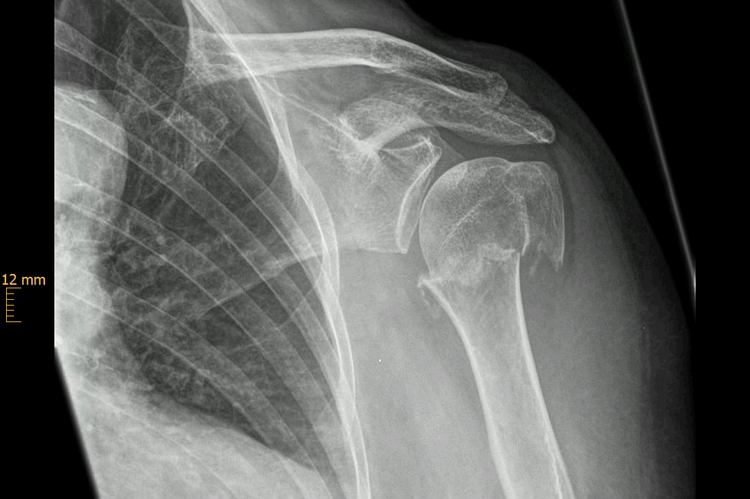

Oberarmfrakturen sind häufige Frakturen der älteren Menschen. Mit der Radiusfraktur (Handgelenk), den hüftgelenknahen Frakturen und den Wirbelkörperfakturen gehören sie zu den häufigsten osteoporotischen Extremitätenfrakturen. Durch ein Sturzgeschehen mit Anprall auf den Ellenbogen oder das Abfangen des Sturzes auf die ausgestreckte Hand entsteht eine axiale Krafteinwirkung auf die Schulter, die zur Fraktur führt (Niedrigenergietrauma). Bei jüngeren Patienten sind es häufig Stürze im Rahmen von Sport- oder Verkehrsunfällen (Hochenergietrauma).

Der große Kopf des Schultergelenkes ist direkt an seinem Übergang zum Schaft des Oberarmes besonders frakturgefährdet. An dieser Stelle kommt es häufig zu Brüchen (subkapitale Humerus-Fraktur).